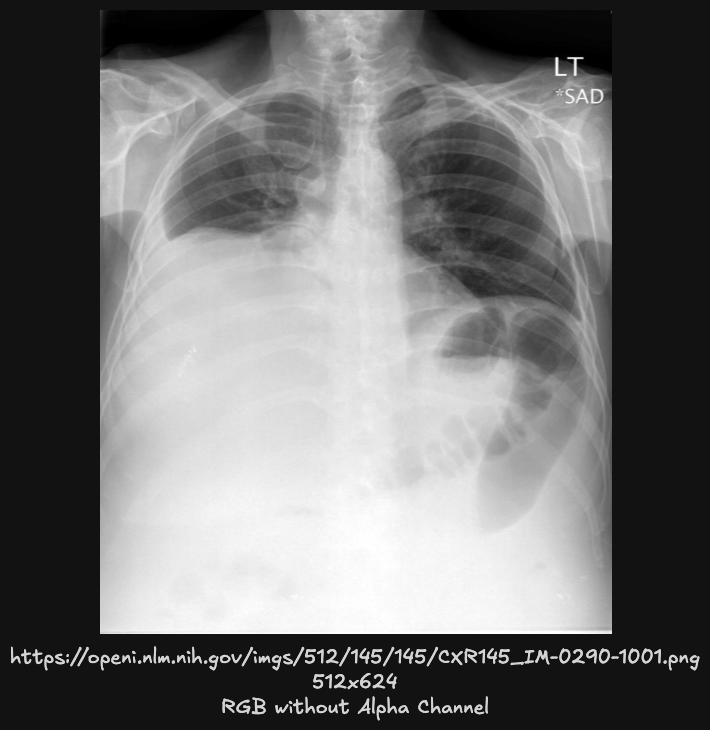

以 https://openi.nlm.nih.gov/imgs/512/145/145/CXR145_IM-0290-1001.png 作为输入图片为例,encode 编码过程可大致分为三步:

preprocess

图像以 Base64 编码的字符串形式批量传递,首先通过 base64.b64decode 解码为二进制数据,然后使用 PIL.Image.open 将其转换为 PIL Image 对象。接着,图像被 resize 到 480 x 480 的大小,并进行转张量及 normalize 操作,使其符合模型输入要求。

此阶段输出的张量形状为 [1, 3, 480, 480],其中 1 是批次大小,3 是图像的通道数(RGB),480 x 480 是图像尺寸。